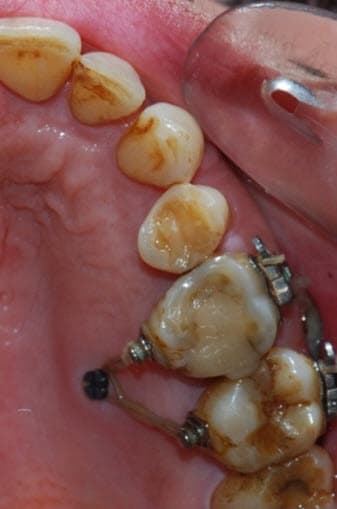

Absolument !

Pour ingresser des secondes molaires supérieures, il faut placer deux microvis en vestibulaire dans le processus zygomatique avec un CS8-1 ou un CS8-2 qui émerge en fond de vestibule, une vis transmuqueuse en palatin. On peut coller des boutons avec tractions élastiques en vestibulaire et en palatin, ou placer une chaînette élastomérique en hamac (voir les photos jointes réalisées je jour de l’intervention). On la colle alors sur la face occlusale par précaution avec une goutte de composite fluide afin qu'elle ne glisse pas. La technique chirurgicale, archi-simple est bien décrite dans le dernier article que nous avons publié (décembre 2016) et pour lequel je te mets un lien DropBox. Une simple anesthésie locale suffit et il n'y a aucun risque anatomique.

Le fait de mettre deux vis permet de déporter le crochet de suspension plus en distal pour tracter la 7.